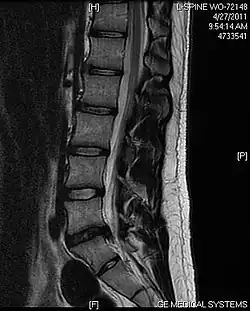

L'imagerie par résonance magnétique peut montrer la hernie, le canal vertébral, les nerfs, les tissus environnants. Les tissus mous sont les mieux analysés par cet examen qui est le plus performant pour le diagnostic de hernie discale. Les images pondérées en T2 montrent clairement la hernie.

IRM cervicale sagittale montrant une hernie discale de niveau C5-C6.